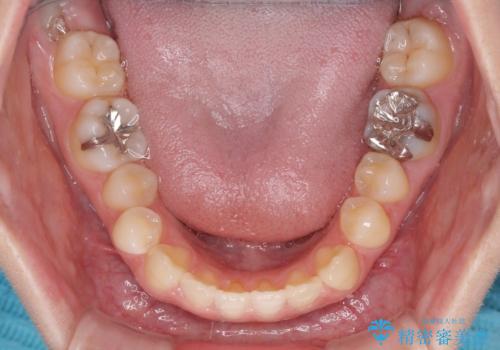

前歯のクロスバイト インビザラインによる矯正治療

- 前歯のクロスバイトとデコボコを気にして来院された患者様です。

骨格的に下顎前突傾向であるため、自己管理が煩わしくないようであれば、インビザラインによる矯正治療がお勧めとなります。

インビザラインを用い、下顎歯列を後方に移動させながら全市の被蓋を改善し、歯並びを整えていくこととしました。

途中マウスピースが使用できず、来院されない期間があり、治療期間は長くかかりましたが、無事に治療を終えることができました。